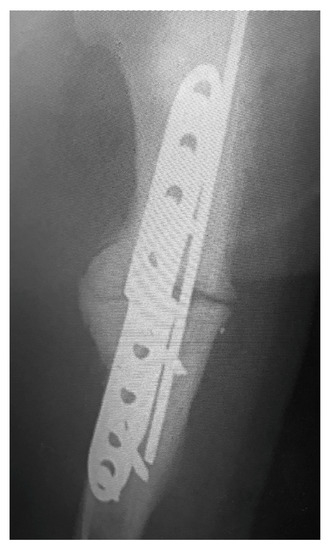

Clinical examinations were also performed at 2, 6, 8, 12, and 14 weeks after surgery. Radiographs of the elbows were taken pre- and post-operative at 6 and 12 weeks (Figure 2 and Figure 3). The owners were asked to assess the dog using a telephone questionnaire (Canine Brief Pain Inventory).

Vetsci 10 00070 g002

Figure 3. Post-operative view of callus formation.